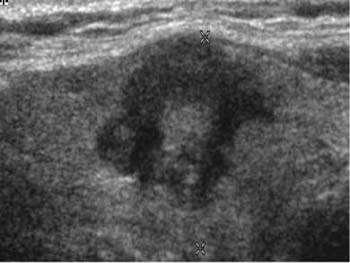

Papilläre und medulläre Karzinome metastasieren mitunter auch in die angrenzenden Lymphknoten, was im Ultraschall

oder auch im MR

zur Darstellung kommen kann. Papilläre und medulläre Karzinome können schon in jugendlichem Alter auftreten.